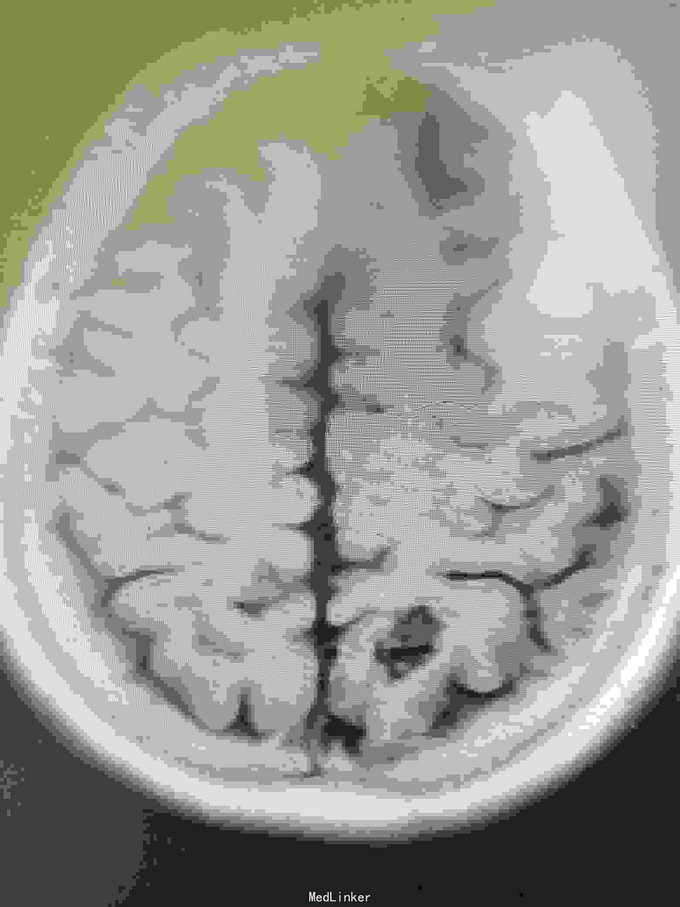

女性,65岁。入院前半年查出AvM,半年后出血入院。

神清,视力视野正常,右侧轻偏瘫。

左枕顶区AVM。 左大脑后及左大脑前供血,深部静脉回流。